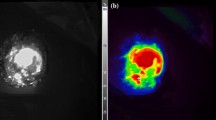

Comparative study showed that a macroscopic metastasis measuring 6 × 7 mm in diameter in the omentum could be detected not only by fluorescence imaging with XenoLight CF750-cetruximab but also by MRI (Fig. 4a). On the other hand, a micrometastasis 1–2 mm in diameter could be visualized by optical imaging but not specified by MRI with both 3D MIP images and 2D T2-weighted images (Fig. 4b). These results thereby indicate the higher sensitivity of optical imaging than MRI in micrometastases.

Comparison of optical and MRI imaging for peritoneal metastasis. a MRI (left), luminescence (center), and fluorescence images (right) of macroscopic peritoneal metastasis 6 × 7 mm in diameter. Peritoneal metastasis in the omentum (arrows) is detected by MRI and fluorescence imaging using XenoLight CF750-cetuximab. MRI images are represented as 3D MIP (maximum intensity projection) image and 2D fat-suppressed T2-weighted image. b MRI (left), fluorescence (center), and autopsy images (right) of micrometastasis 1–2 mm in diameter. Peritoneal metastasis can be visualized by fluorescence imaging with the aid of a covering sheet to reduce autofluorescence but is unclear by MRI image. MRI images are represented as MIP image and 2D fat-suppressed T2-weighted image